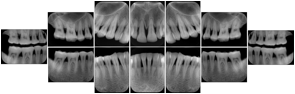

OO.1.3 Cardiology

Cardiac stress testing acquires images in at least two patient states, rest and stress, and typically with several different views of the heart to highlight function of different cardiac anatomic regions. Image review typically involves simultaneous display of the same anatomy at two patient states, or multiple anatomic views at one patient state, or even simultaneous display of multiple anatomic views at multiple states. This applies to all cardiac imaging modalities, including ultrasound, nuclear, and MR. The American College of Cardiology and American Society of Nuclear Medicine have adopted standard display layouts for nuclear cardiology rest-stress studies.